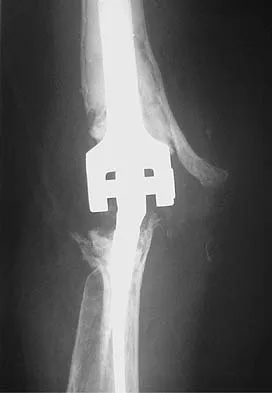

A 66-year-old woman who requires a cane for ambulation now notes increasing difficulty in using the cane after undergoing total elbow arthroplasty 3 months ago. AP and lateral radiographs are shown in Figures 15a and 15b. What is the most likely diagnosis?